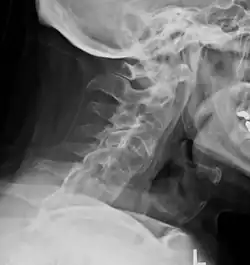

Lateral X-ray of the neck in ankylosing spondylitis -

Cervical spine showing ankylosis (fusion) -

The earliest changes demonstrable by plain X-ray shows erosions and sclerosis in sacroiliac joints. Progression of the erosions leads to widening of the joint space and bony sclerosis. X-ray spine can reveal squaring of vertebrae with bony spur formation called syndesmophyte. This causes the "bamboo spine" appearance. A drawback of X-ray diagnosis is the signs and symptoms of AS have usually been established as long as 7–10 years prior to X-ray-evident changes occurring on a plain film X-ray, which means a delay of as long as 10 years before adequate therapies can be introduced.[26]